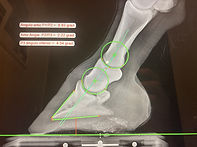

IMAGIOLOGIA (com Radiologia e Ecografia)

Temos ao seu dispôr equipamento de radiografia digital, ecografia e endoscopia. Tudo portátil e com toda a conveniência para as consultas ao domicílio. Em exames em acto-de-compra podemos dar resposta ás suas questões no próprio dia. Em caso pontuais onde seja necessário exames de ressonância magnética, TAC ou cintigrafia nuclear trabalhamos com vários centros na Europa de modo a ajustar ás necessidades de cada caso.